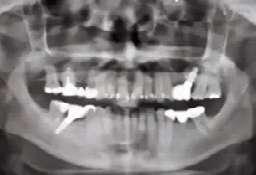

Se llevó a cabo el protocolo convencional de radiografías periapicales y radiografía panorámica, en las cuales se observó el desajuste y la fractura de los muñones anterosuperiores.

caso clínicoPRÓTESIS 32 eldentistamoderno mayo/junio 2024

Basándonos en el examen clínico y radiográfico, se opta por retirar la prótesis fija superior y realizar las extracciones de los dientes fracturados, así como la eliminación de caries y cambio de amalgamas. Se realiza fase de saneamiento eliminando caries y restauraciones defectuosas, dando lugar así a un edentulismo parcial de la arcada superior (Fig. 1a, 1b). Después de efectuar el diagnóstico y anamnesis se decide no colocar implantes y hacer una prótesis removible retenida por coronas telescópicas friccionales.